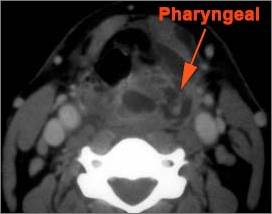

Retropharyngeal Lymph Nodes

If there is suppurative retropharyngeal adenopathy what is the maximum short axis dimension of the largest suppurative node. MEASUREMENT